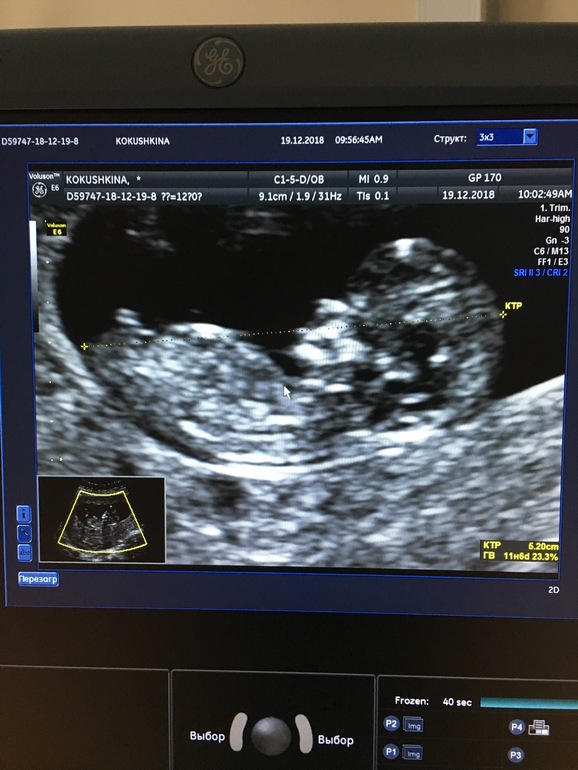

Фото узи в 11,6 недель и в 13.1 неделю

1. 11,6 недель

2. 13.1 неделя